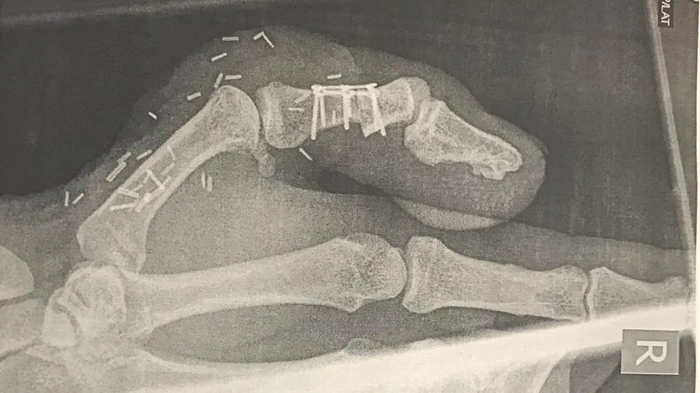

엄지손가락 절단 사고를 겪은 영국 남성 데이비드 리의 접합 수술 후 엑스레이 사진. 사진=데이비드 리 / BBC 방송 캡처